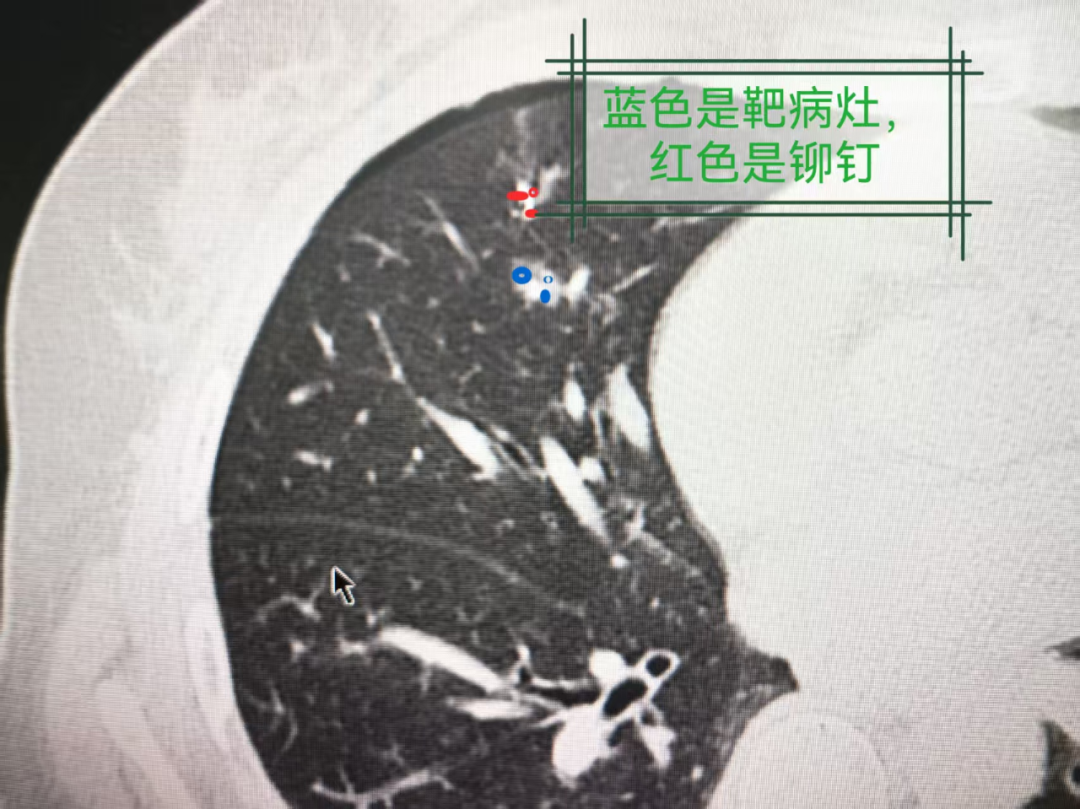

图2:同一CT层面的肺窗图像

图3:同一CT层面的肺窗图像

图4:同一CT层面的肺窗图像